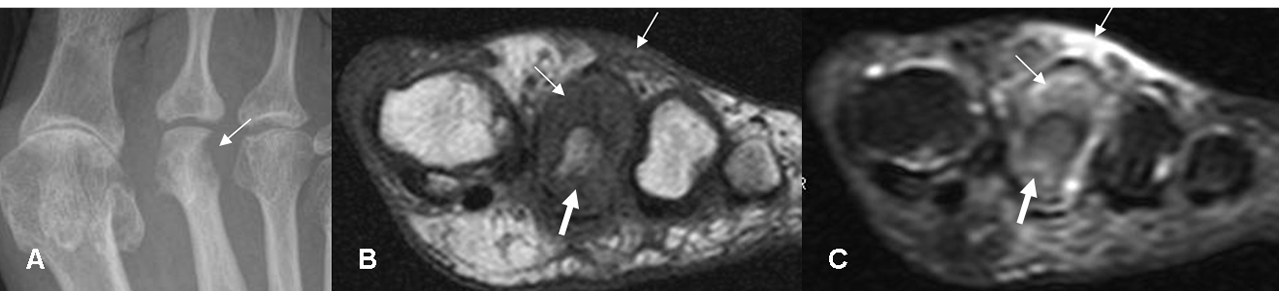

Fig 34. Osteomielitis.

A: Rx AP. Osteolisis en la parte lateral de la cabeza del 2º metatarsiano.

B: RM axial en T1 y C: RM axial en STIR. Cambios inflamatorios en el tejido celular subcutáneo y rodeando la cabeza del metatarsiano. (Flechas delgadas). El hueso muestra erosión en su parte posterior y edema trabecular, por osteomielitis. (Flechas gruesas).